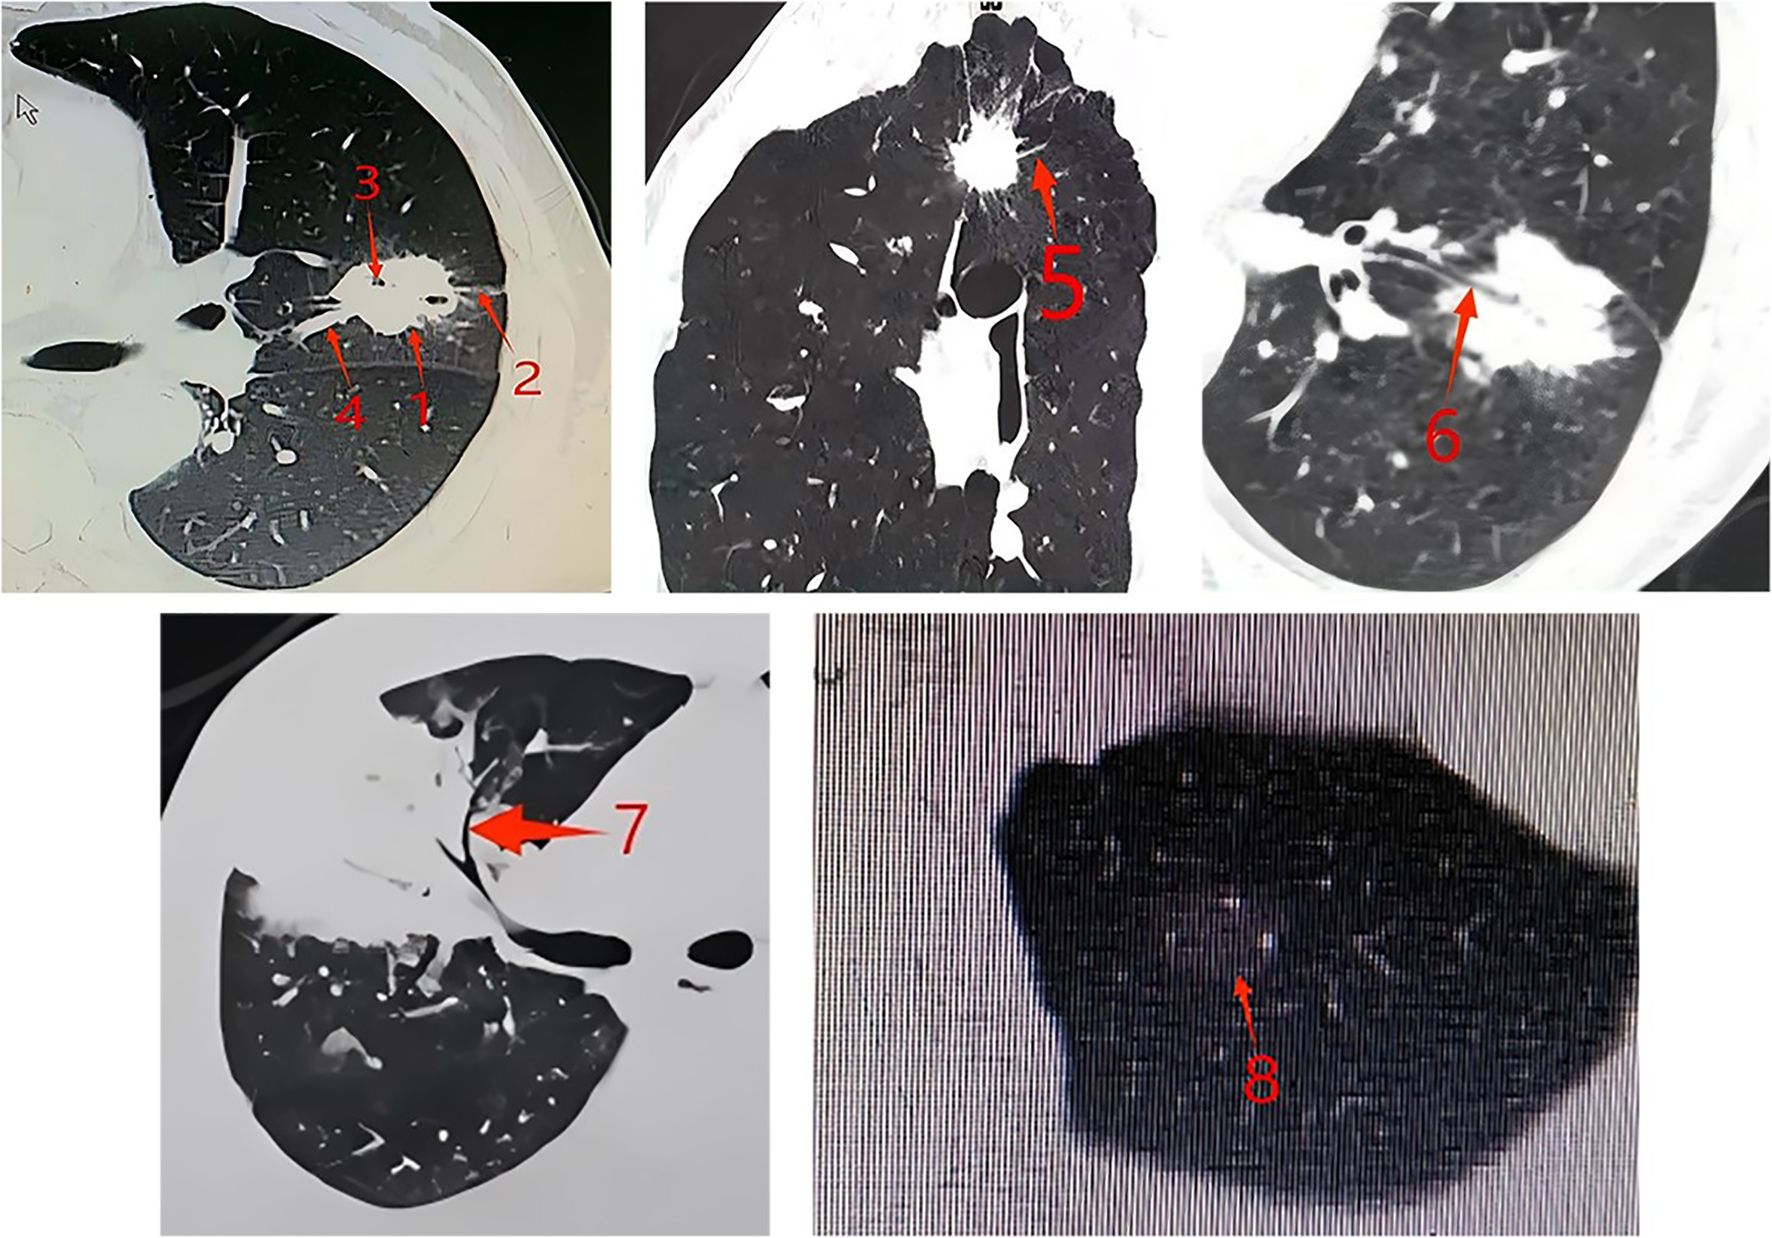

Objective: This study aimed to explore the relationship between EGFR mutations, ALK positivity, and demographic, tumor, radiological, and pathological characteristics in lung adenocarcinoma patients. Methods: This study included 626 patients with early-stage lung adenocarcinoma who underwent surgical resection between October 2017 and December 2023.EGFR and ALK mutations were analyzed postoperatively. Clinical, pathological, and imaging features such as gender, age, smoking status, and tumor characteristics were assessed. Patients were categorized based on their mutation status, and comparisons were made regarding their clinical and imaging features. Results: Results indicated that EGFR-positive patients were predominantly female, younger, and had a higher frequency of non-smokers compared to the wild-type (WT) group. EGFR mutations, particularly the exon 19 deletions and L858R mutations, were more common in patients with moderate differentiation and lepidic or acinar predominant histological subtypes. CT imaging revealed that EGFR-positive tumors were smaller in size and had fewer solid components compared to WT tumors. Additionally, certain CT features such as the spicule sign and air bronchogram were significantly associated with EGFR mutations. For ALK mutations, the analysis showed that patients with ALK-positive tumors had distinct radiological features, including a higher occurrence in the lower lobes and fewer ground glass nodules compared to the WT group. Conclusions: The study concluded that specific radiological and pathological characteristics, along with EGFR and ALK mutation statuses, could be used to guide the treatment and diagnosis of lung adenocarcinoma.